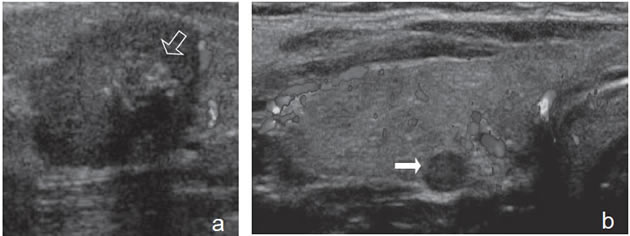

Figura 13. a) Cáncer papilar sólido,

con vascularización central (flecha) con

vasos intranodulares desorganizados;

b) Cáncer papilar sólido delimitado por

vasos periféricos y un vaso central penetrante

de mayor tamaño (flecha); c)

Nódulo coloideo con un patrón de flujo

mixto, periférico y vasos centrales desorganizados

(flechas) que simulan un

patrón maligno; d) Hiperplasia folicular

que muestra un nódulo bien delimitado

con vascularización aumentada,

central y periférica